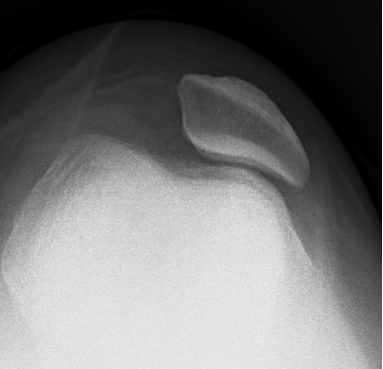

随着现在体育运动的增加,儿童意外伤害也越来越多,其中“膝盖骨”脱位也逐年增加。“膝盖骨”脱位在医学上称之为髌骨脱位,其定义为髌骨因外伤因素或自身韧带松弛等因素导致其偏离原来的解剖位置,从而产生一系列膝关节疼痛、肿胀、活动受限等症状的疾病。(如下图所示)

1、X 线片

对诊断有很大价值,可以显示髌骨形态和位置是否正常,常规应拍膝关节正侧位及髌骨轴位 X 线片,髌骨轴位X线片对髌骨向外侧偏斜及半脱位有肯定的意义,可显示髌骨及滑车发育不良,髌股关节面不相适应及髌骨移位情况,可通过测量髌骨脱位相关角度,以明确诊断。

正常髌骨

脱位髌骨